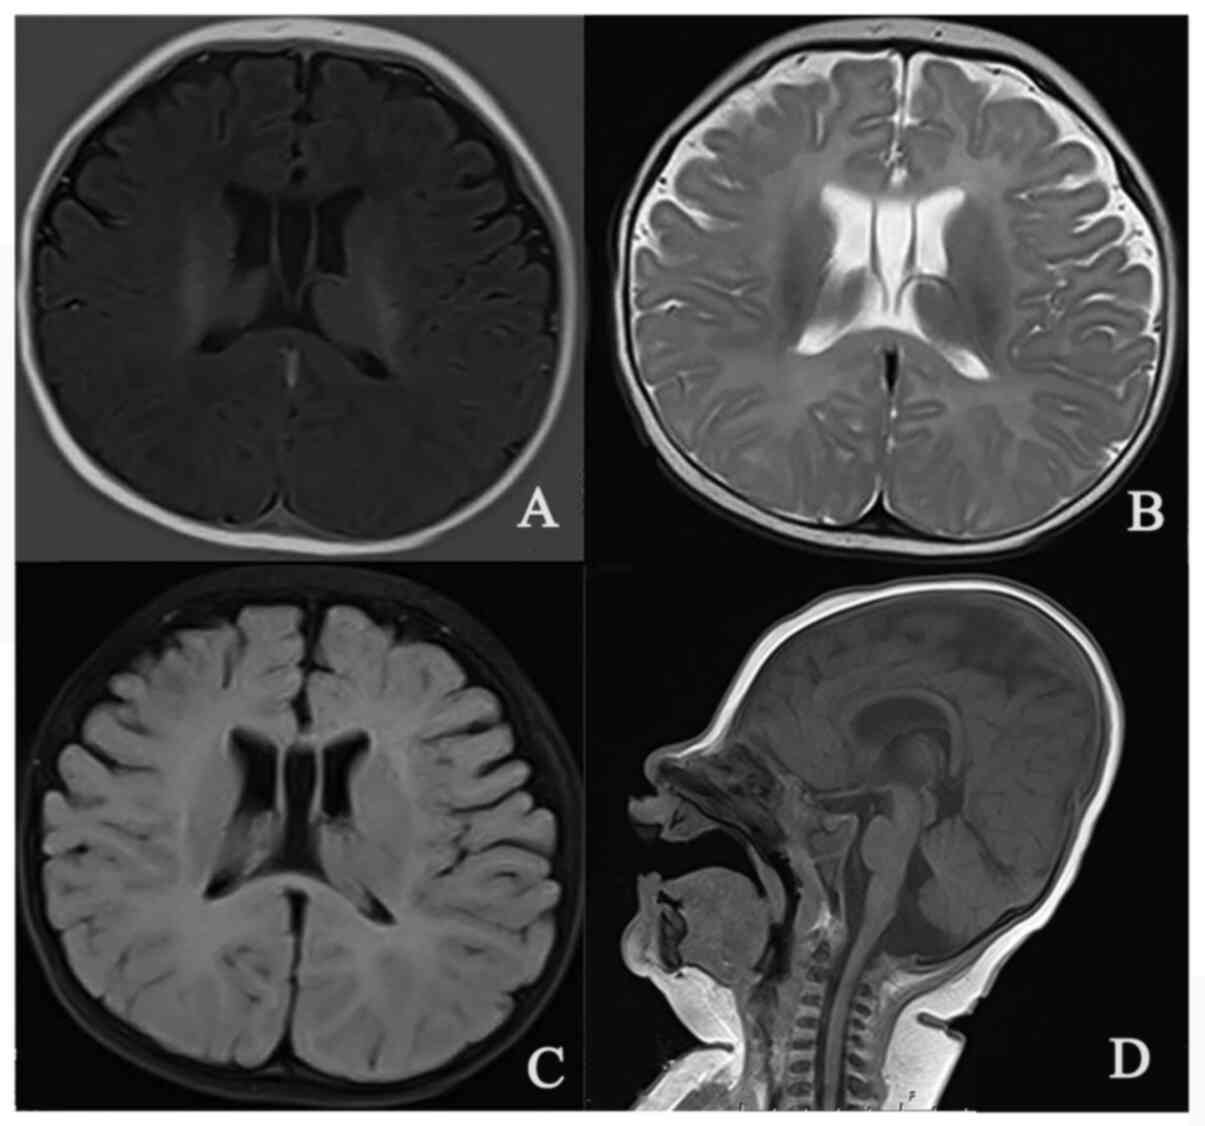

First Chinese patient with mental retardation‑40 due to a de novo CHAMP1 frameshift mutation: Case report and literature review

Mental retardation‑40 (MRD40) is a rare autosomal dominant neurodevelopmental disorder with a poor prognosis that is caused by a heterozygous mutation in chromosome alignment maintaining phosphoprotein 1 (CHAMP1). It was previously considered a non‑syndromic disease due to the lack of specific external features. Only limited international reports describing CHAMP1 mutations are currently available. The present case study was the first to report on a Chinese patient with MRD40. The patient presented with severe global development delay with significant craniofacial dysmorphia. Using trio whole‑exome sequencing, a novel de novo frameshift mutation in CHAMP1, NM_032436.2: c.530delCinsTTT, was identified, which expands the spectrum of the known pathogenic variants. The present case report helps to improve the syndromic profile of the rare MRD40 disorder and provides an example for the clinical diagnosis of MRD40.

Figure 1

Figure 2

Figure 3